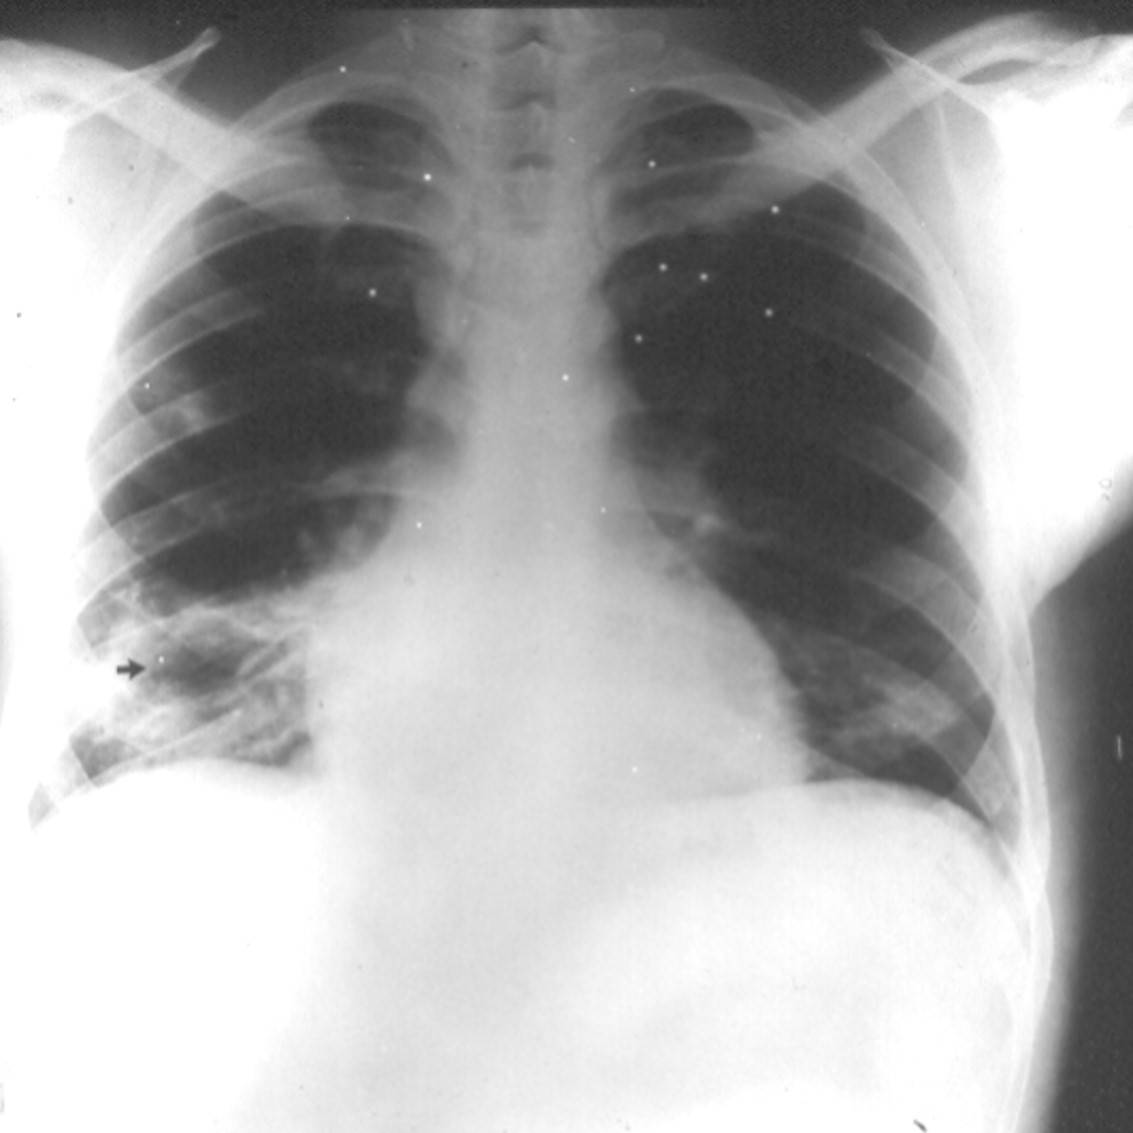

While practicing Telemedicine, you are asked to make a diagnosis in a 22-year-old

man from New York City who presents with a two week history of fever, rigors, and

fleeting pleritic chest pains involving both lungs. You are shown his chest x-ray

and given a recording of his heart (see below) but are provided no other information.

The patient's chest x-ray shows evidence of right atrial enlargement, a right lower lobe abscess (arrow), and patchy infiltrates in the right upper lobe and the left lower lobe. The tiny white dots are artifacts.